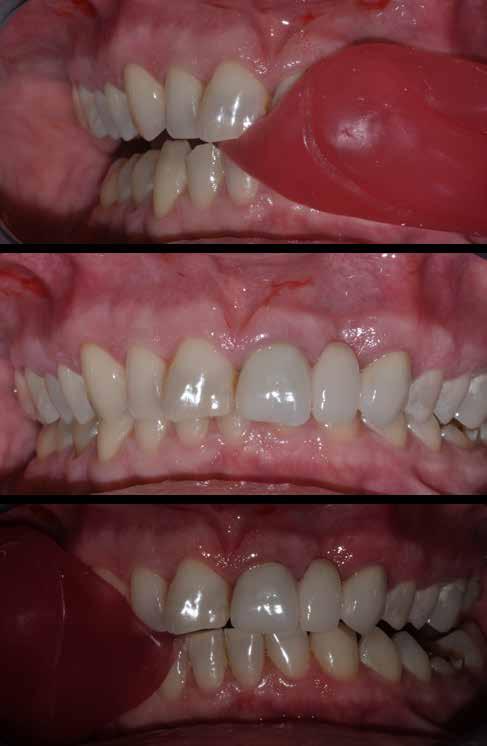

Az 53 éves hölgy páciens jobb felső 6-os fogában látható amalgámtömés cseréje volt a cél. A tömés mellett secunder caries és az amalgám következtében létrejött mesialis zárólécen áthaladó repedés, továbbá mesialis caries figyelhető meg (1. ábra). El kellett kerülni, hogy a tömés kifúrásakor az amalgámtörmelék a páciens szájába kerüljön, esetleg ebből valamennyit lenyeljen, a kezelés első lépésként kofferdám izoláció került fel a jobb felső kvadránsba (2. ábra). A kapocs a 1.7 fogra került, ezzel kényelmesen helyet teremtett a későbbiekben felkerülő matricarendszernek. Az egyszerre több fog izolálása lehetővé teszi, hogy a szomszédos fogak referenciául szolgáljanak a restauráció felépítése közben.

A régi amalgámtömés eltávolítását követően caries indikátor segítette a carieses laesio megfelelő kitisztítását a pulpa expozíciója nélkül. Ezután kerülhetett sor az ideális üregdesign kialakítására, továbbá a zománcszélek finírozására (3. ábra) Az approximális box megnyitása során az alátámasztatlan zománcprizmák eltávolításra kerültek, ezzel is csökkentve a secunder caries képződés veszélyét. Az így kialakuló forma elősegíti a matrica megfelelő adaptációját, végül pedig az approximális box határainak a hozzáférhetőségét, így finírozás során ez jobban kontrollálható és polírozható.

A Palodent V3 matricarendszer felhelyezését követően a zománc 10 másodperces szelektív savazása, majd lemosása és leszárítása után történt a kavítás bondozása Prime & Bond Universallal.

Kulcslépés: a II. osztályú üreget a matricarendszer segítségével I. osztályúvá lehetett átalakítani.

A pontosabb széli záródás érdekében célszerű a matrica illesztési határába némi folyékony kompozitot felvinni (NeoSpectra ST flow A2), majd megvilágítás nélkül a zárólécet paszta kompozittal (NeoSpectra STHV A2) felépíteni, miközben a kifolyó fölösleges folyékony kompozit eltávolításra kerülhet. Így ki lehetett használni és kombinálni a két különböző konzisztencia előnyeit.

A polimerizációt követően kerülhet sor a matricafeszítő gyűrű, valamint a matrica eltávolítására. A Palodent V3 fülekkel ellátott matrica kialakításának és a speciális PinTweezers csipesznek hála, a feszes kontaktpont ellenére a matrica könnyedén eltávolítható. Az éket viszont a kezelés végéig

célszerű bennhagyni, elkerülve egy esetleges nemkívánatos vérzést (4. ábra)

A matrica és gyűrű nélkül az approximális fal magassága, valamint a szomszédos fogakhoz viszonyítható dimenziók jobban megállapíthatóak. A jobb térlátás és a nagyobb mozgástér precízebb eredményhez vezet, csökkentve ezzel az utólagos finírozás mértékét, továbbá a részletgazdagon kialakított anatómiai struktúrák torzulásának az esélyét. Az üreg mélyebb részei SDR Plus A3-mal kerültek feltöltésre, majd NeoSpectra STLV A3-mal kiegészítve vált teljessé a dentin pótlása (5. ábra), ezzel létre lehetett hozni egy homorú formájú kromatikusabb alapot.

Ezt követően csücsökről csücsökre haladva a felső hatosokra jellemző anatómiai struktúrák, megfelelő orientációval bíró csücsöklejtők és elsődleges barázdák Neo Spectra

HV A2 anyagból kerültek kialakításra (6. ábra). Apró „kompozit-hurkákkal” kiegészítve létrehozható a csücskökön belüli tagoltság, ezzel kialakítva a másodlagos barázdarendszert és egy sokkal kidolgozottabb anatómiai struktúrát (7. ábra). A fogorvos esetleges „művészi hajlamát” is figyelembe véve, a természethű megjelenés barázdafestéssel (Micerium - Stain Brown 2) még tökéletesebb lehet (8. ábra). Ezzel a korábban részletgazdagon kialakított ba-

rázdarendszer kiemelhető, és optikailag fokozható a gödröcskék mélysége is.

A restauráció megfelelő polimerizációja után célszerű a kofferdám nyújtotta retrakciót kihasználni, és a restauráció széli záródásában levő esetleges kompozitfölösleg elfinírozását jobb rálátás mellett elvégezni (9. ábra). Ebben nagy segítségünkre lehet az Enhance rendszer, mely a kompozitot nagyon szépen elsimítja, de a természetes fogszövetet nem bántja.

A matricázott terület széli záródásának a kidolgozásában az EVA polírozó (10. ábra) lehet a segítségünkre, amellyel a gingiva sérülése megelőzhető, és a kialakított feszes kontaktpont sem kerül redukcióra (11-12. ábra)

A kofferdam eltávolítását követően kerülhetett sor az occlusio beállítására csücsöklejtők domborúságának a redukciója révén (13. ábra). A harapás gyémántfúrókkal történő beállítása után a polírozás Enhance rendszerrel történt, melynek végső lépéseként a PrismaGloss használatával (14. ábra) nyerhette el a restauráció a végső fényességét (15. ábra)

A ma rendelkezésre álló modern eszközöknek és anyagoknak hála II. osztályú üregek direkt módon kiszámíthatóan restaurálhatóak. A matricarendszernek köszönhetően helyreállítható a feszes kontaktpont, a „kaméleon effektussal” bíró kompozit pedig a tömés integrációjáért felel. A megfelelő adhézió, a precízen kidolgozott széli záródás és a plakkréteg megtapadását nehezítő polírozott felszín a kezelés hosszú távú sikerének a garanciája. Mindezek együtt egy hosszú távon tartós, funkcionális és esztétikai rehabilitálást tesznek lehetővé.